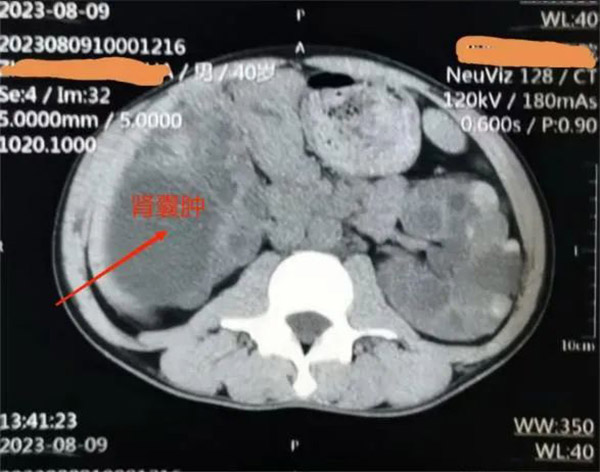

▲患者肾囊肿影像

肾内科主任洪敏接诊后,对王先生进行了详细的检查,结合其病情和身体情况,决定实施超声引导下经皮穿刺抽液囊肿硬化治疗。

“超声引导下经皮穿刺抽液硬化治疗能清晰显示囊肿的位置、大小、深度以及和周围脏器的关系,实时观察穿刺治疗过程,操作简便、安全,无辐射,更适合不愿接受外科手术的王先生。”洪敏主任表示。